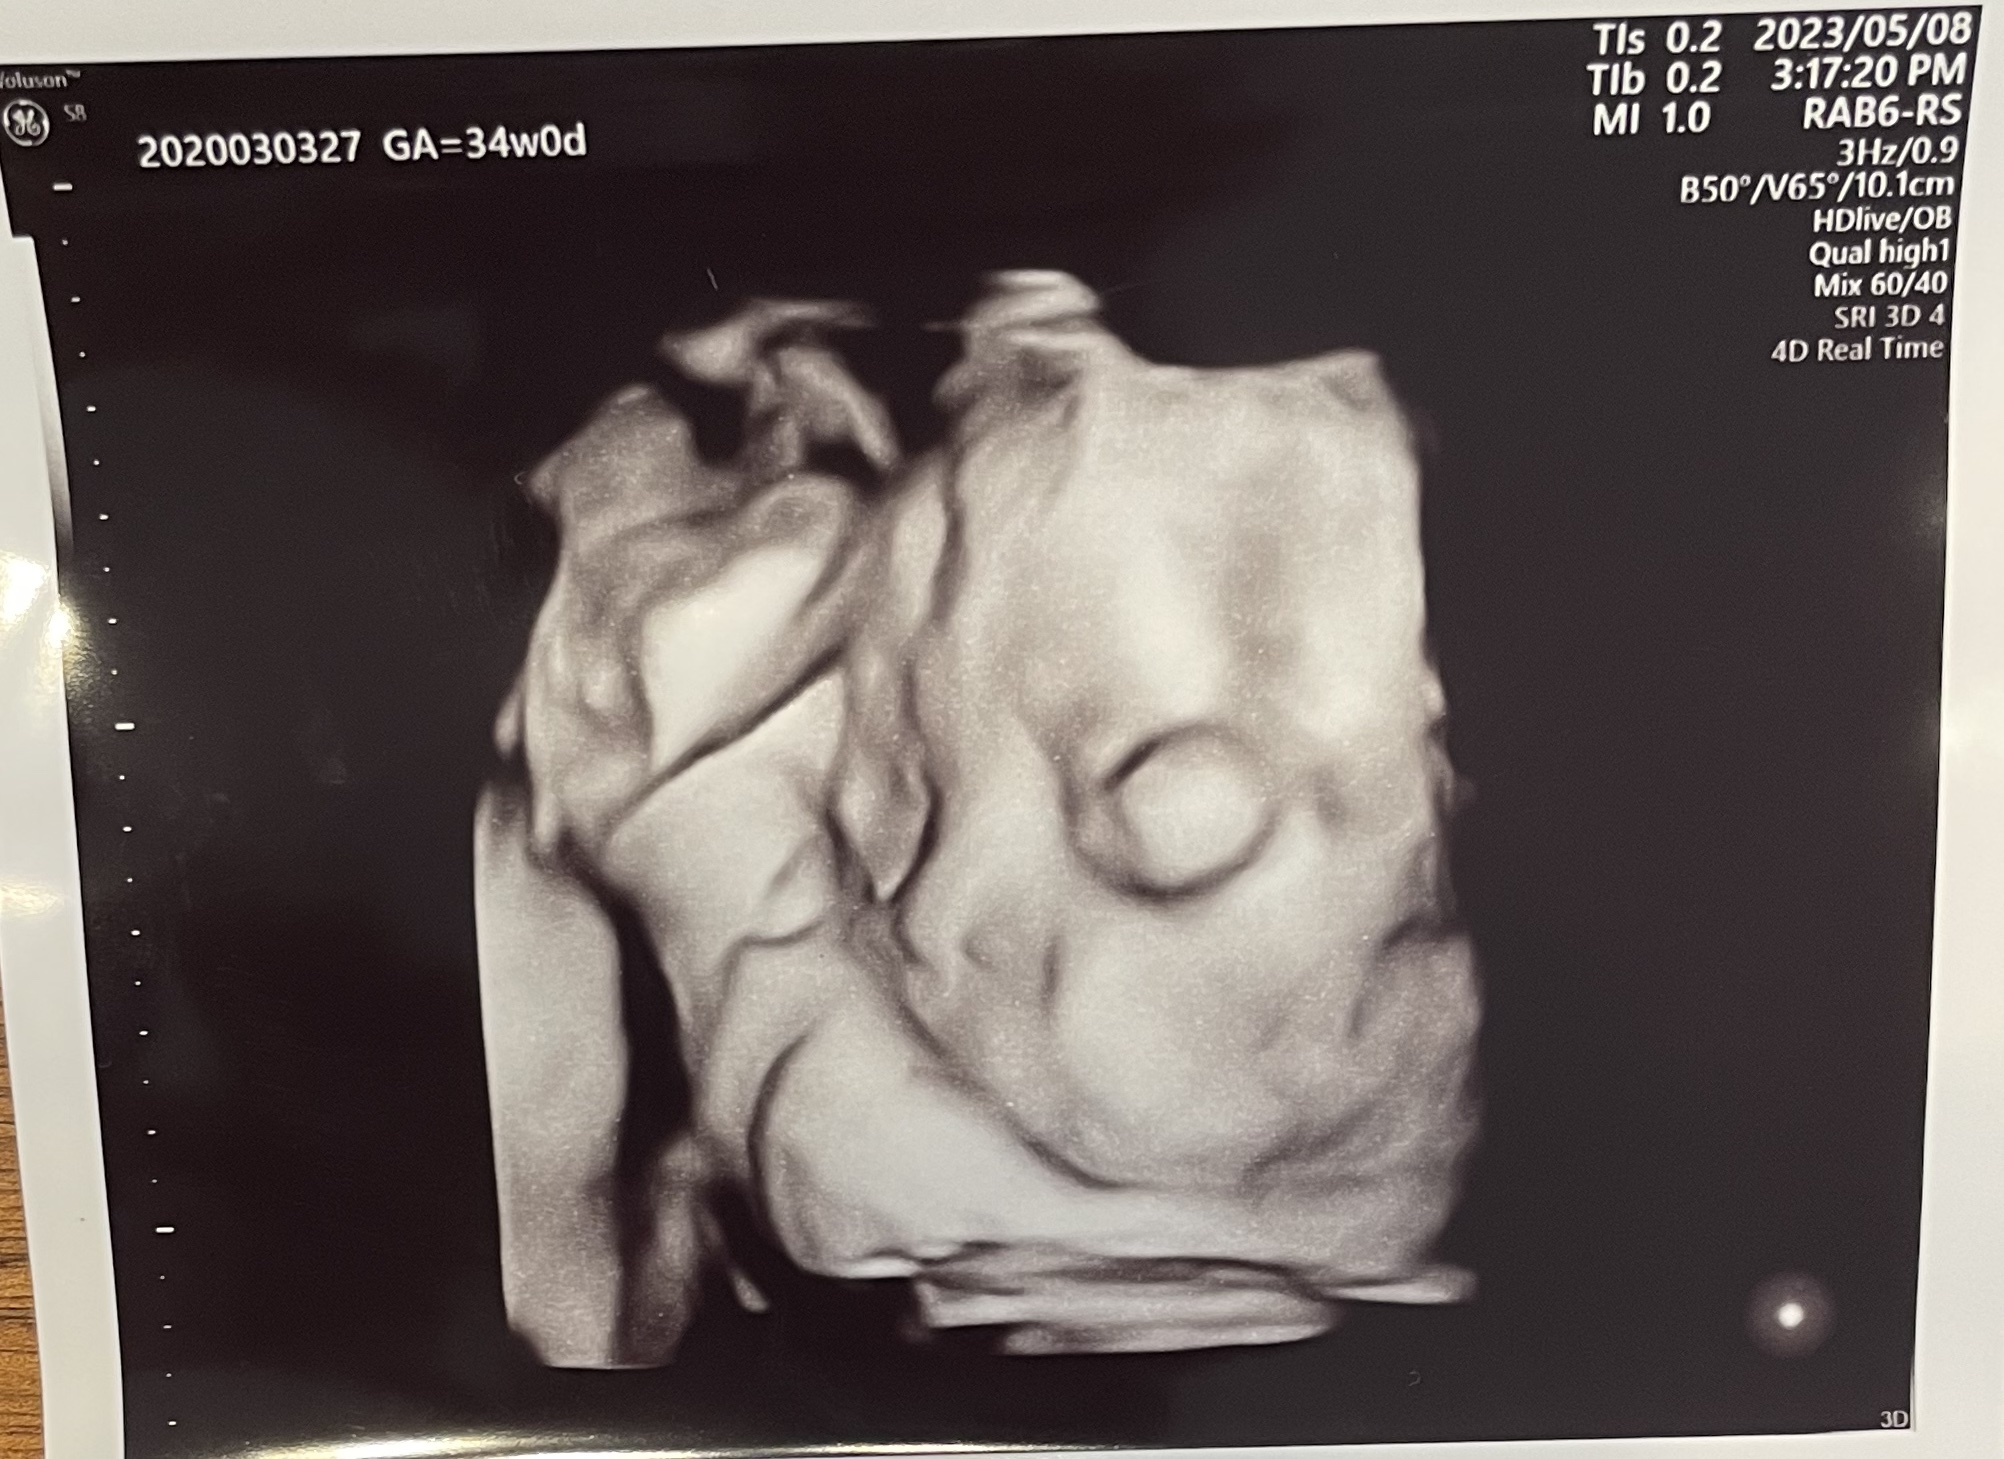

4Dのエコーの最中にお腹の中で赤ちゃんがすごく動いていて、映像が乱れていたのが怖かったです^^;

一応解説すると、向かって右側を向いていて、飛び出た丸いものが目です。笑

これを印刷してくれる先生のユーモア?は、なかなか気に入っています。